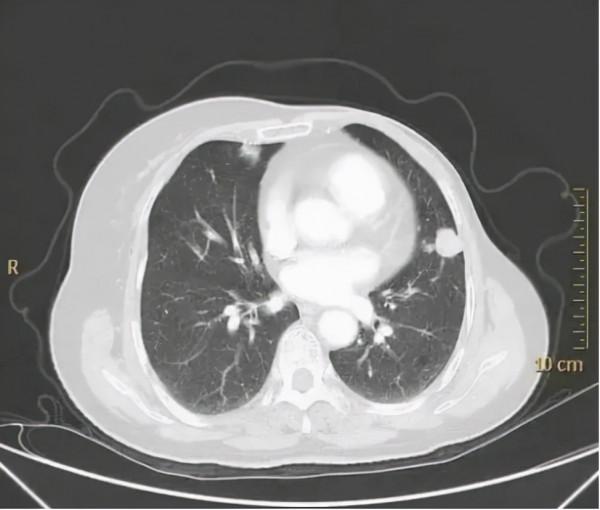

2020年3月崔女士因反覆刺激性乾咳到醫院就醫,複查胸部CT提示:兩肺內見多發類圓形結節影,最大者位於左肺下葉,直徑約1.5cm,考慮兩肺多發轉移癌。